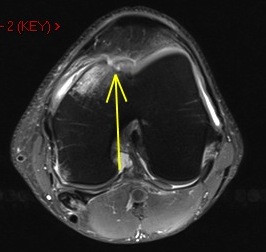

36 y/o was running and struck by car

Osteochondral fracture of the medial femoral trochlea. Notice the displaced chondral fragment behind the lateral femoral condyle interposed between the condyle and the posterior lateral capsule. Moral of the story – if you see an acute defect, look for the fragment.

Osteochondral fracture femur with displaced fragment